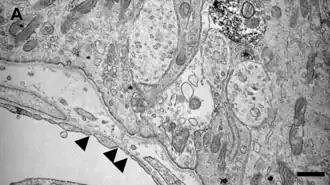

Los NHO presentan capilares fenestrados con poros en su endotelio, de 30-80 nanómetros (nm) de diámetro. Estas fenestraciones se encuentran cubiertas por prolongaciones de las células perivasculares pericitos/tanicitos en los órganos NH sensoriales.[5]

La microscopía electrónica ha demostrado que los CVO-Sn, presentan poros en el endotelio de 30 a 80 nanómetros (nm) de diámetro. Estas fenestraciones se encuentran cubiertas por prolongaciones de las células perivasculares similares a pericitos/tanicitos.[5]